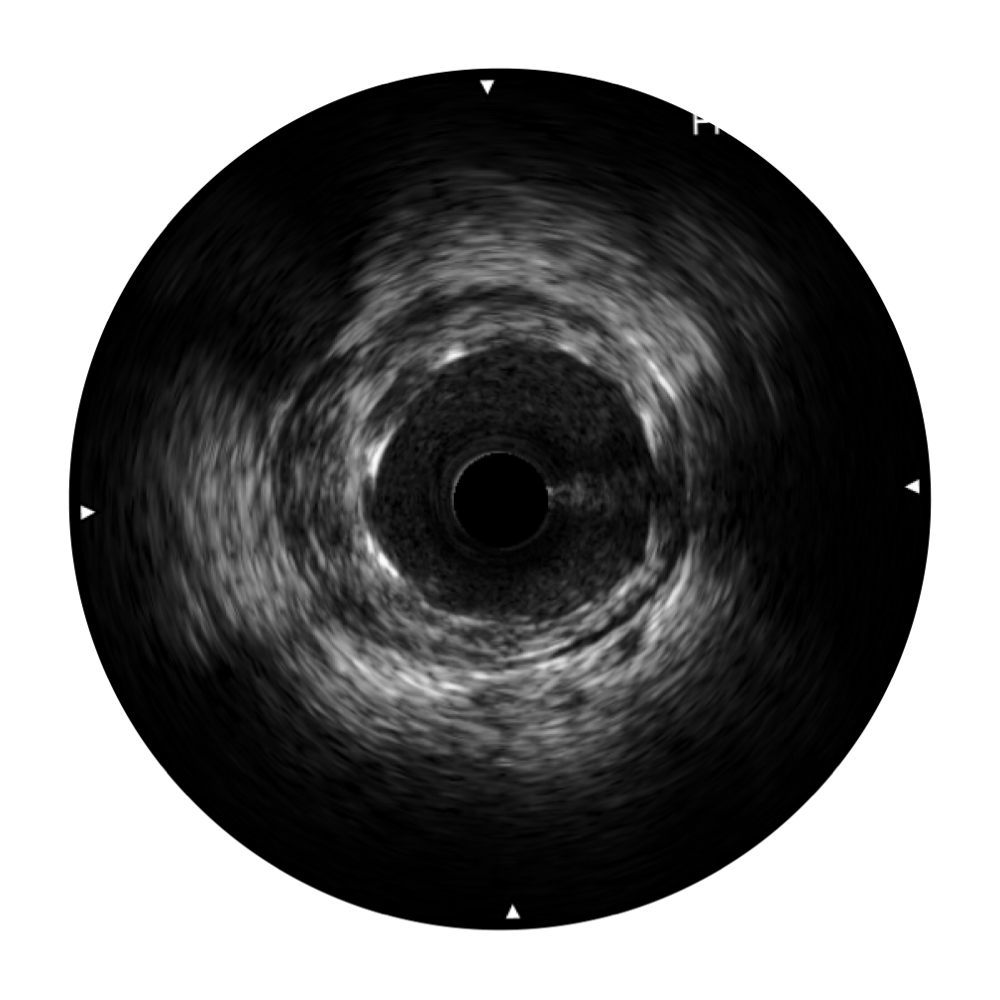

美狮贵宾会官网宽频IVUS图像

对比传统IVUS导管成像,美狮贵宾会官网宽频IVUS图像的近场支架梁显影更细腻,远场中膜外血管仍清晰可辨,兼顾远中近,兼顾分辨力与穿透深度